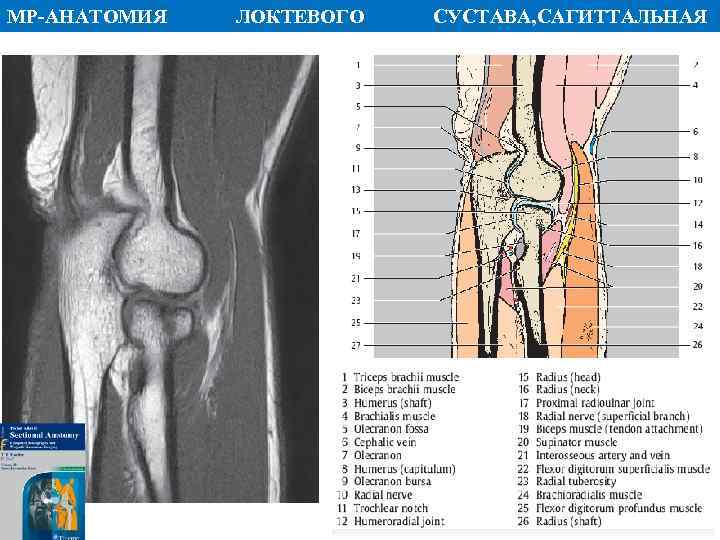

МР АНАТОМИЯ ПЛОСКОСТЬ ЛОКТЕВОГО СУСТАВА, САГИТТАЛЬНАЯ

МР АНАТОМИЯ ПЛОСКОСТЬ ЛОКТЕВОГО СУСТАВА, САГИТТАЛЬНАЯ